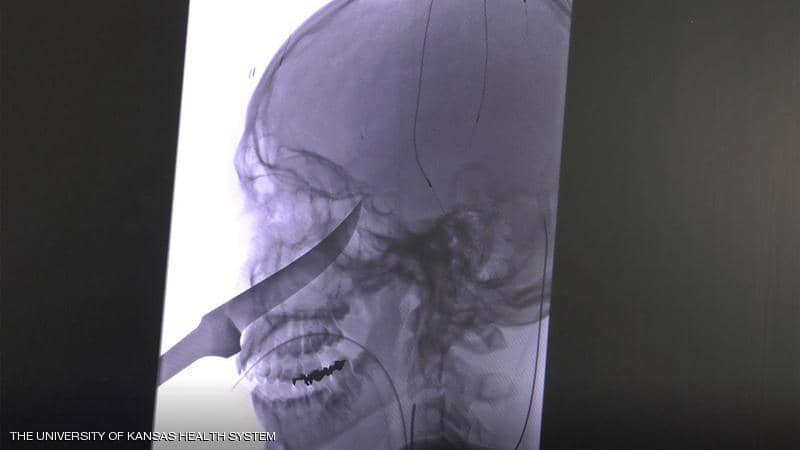

| سكين طوله 25 سنتيمترا في الجمجمة .. كيف نجا هذا المراهق؟ |

| 18-06-2019 10:34 AM |

نجح فريق طبي أميركي في إنقاذ حياة مراهق من ولاية كانساس، تم نقله إلى المستشفى بينما كان سكين طوله 25 سنتيمترا يخرج من جمجمته.ونقل موقع فوكس نيوز عن جيمي راسل، والدة إيلي... |